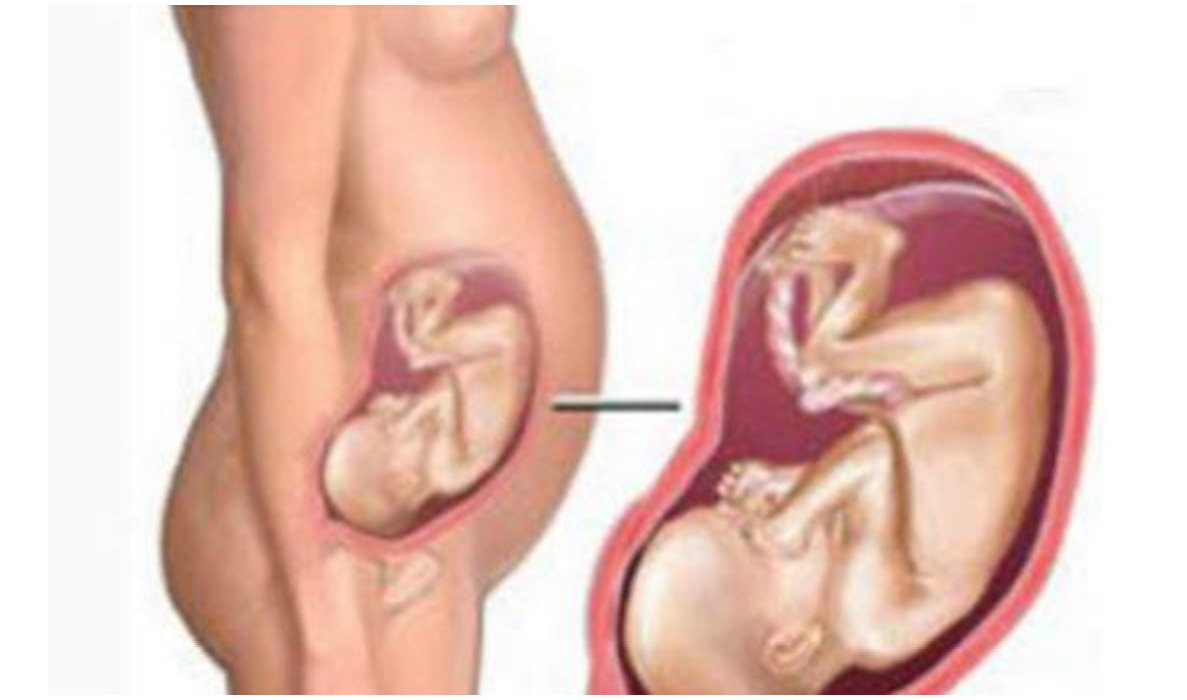

Фотография Плода В Животе

Фотография Плода В Животе 113 фотографий